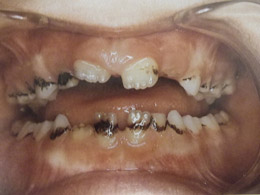

Τερηδόνα βρεφικής και νηπιακής ηλικίας ή τερηδόνα θηλασμού

Η τερηδόνα βρεφικής και νηπιακής ηλικίας εμφανίζεται σε μικρά παιδιά ηλικίας 2 έως 5 ετών, τα οποία έχουν τερηδονισμένα ένα ή και περισσότερα νεογιλά δόντια. Η τερηδόνα αυτής της μορφής οφείλεται σε λάθος τρόπο διατροφής του παιδιού και μπορεί να εξελιχθεί γρήγορα και σε μεγάλη έκταση επηρεάζοντας το σύνολο το δοντιών που βρίσκονται στο στόμα.

Η κυριότερη αιτία εμφάνισης της τερηδόνας αυτής της μορφής είναι το τάισμα με το μπιμπερό ενώ το παιδί κοιμάται. Κατά τη διάρκεια του ύπνου η ποσότητα του σάλιου μειώνεται και το γάλα, ανεξάρτητα αν περιέχει ή όχι ζάχαρη, παραμένει πάνω στα δόντια και προκαλεί τερηδόνα. Ακόμη και το μητρικό γάλα μπορεί να έχει τις ίδιες συνέπειες, εφόσον το παιδί θηλάζει κατά βούληση κατά τη διάρκεια της νύχτας.